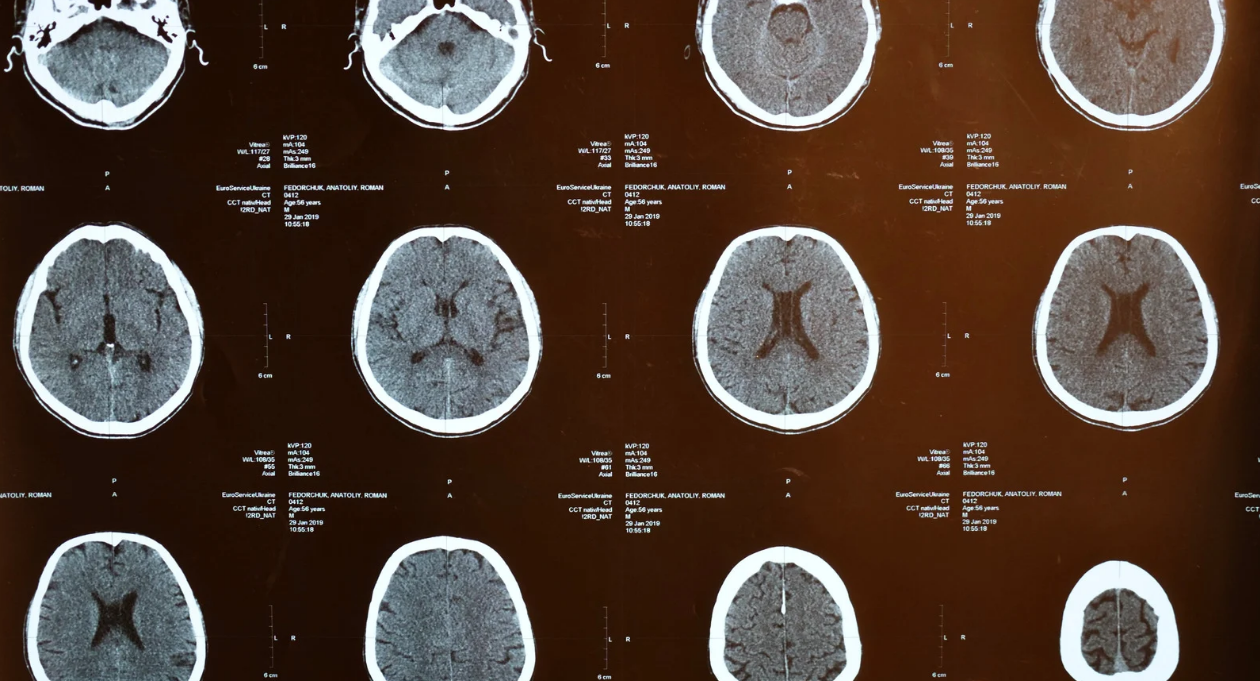

開催日程:2025年9月19日、10月17日、11月21日、12月19日(第三金曜日)20:30~22:00【オンライン開催】 費用 11880円 税込 お申し込みはこちら▼ https://seminar.ep-och.com/products/seminar2610 講師:宮内 貴之先生 湘南医療大学保健医療学部リハビリテーション学科作業療法学専攻 専門作業療法士(脳血管障害) ========== 脳血管疾患を担当する理学療法士や作業療法士は高次脳機能障害の影響を考えながら 日々リハビリを提供していると思います。 その際、脳がどのような損傷を負っているのか、どのような症状が出現するのかを 結果として学んでおられるはずです。そこから先、高次脳機能障害の機能面に踏み込んでどのような機能が残存しているのかを考えたことはありますか? 脳科学的な視点から高次脳機能障害を理解することで、今あなたが担当している患者様がどのような結果、このような症状を呈しているのかをより深く理解することができます。 本セミナーでは2024年に高次脳機能障害の症状についてわかりやすくまとめていただいたシリーズを開催させていただきました。 本セミナーではより具体的に脳科学的にニューロリハビリテーションについて解説していただき、実際の患者様にどのように提供していくかを解説していただきます。 ●●●●●●作業療法士・理学療法士が臨床で悩む脳血管障害の高次脳機能障害を徹底解説●●●●●● 急性期脳卒中後には約80%の方が何らかの高次脳機能障害を呈すると言われています。 急性期リハビリテーションでは脳卒中に限らず、 低酸素脳症や脳症など脳器質病変を伴う疾患を目にする機会も多いのではないでしょうか? 高次脳機能障害は機能予後不良因子であり、 早期からの適切な評価やリハビリテーションが必要となります。 高次脳機能障害といっても注意障害や記憶障害、半側空間無視といった臨床でよく出会う症状から 視覚失認や観念失行などあまり出会わない症状まで多岐に渡ります。 高次脳機能障害のリハビリテーションを行う上で 各症状の原因や評価方法を知らなければ、適切なリハビリテーションの提供には至りません。 また、机上評価のみではなく、実際の生活動作で障害となっている動作をしっかりと評価しなければいけないと思っています。 本セミナーでは高次脳機能障害を考える上で山鳥先生が提唱された 山鳥モデルやラスク研究所が提唱した神経心理ピラミッドを用いることが多いかと思います。 今回はこの2つの考え方を基に進めていき、各症状に対して解説が出来たらと思っています。